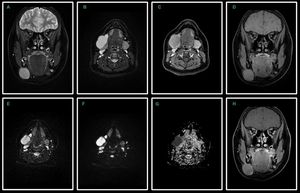

Diffusion-Weighted MR Imaging of the head and neck using Read-out Segmented Echo-Planar Imaging technique. 14-year-old female patient with submandibular tumor. Coronal T2-w FSE Dixon water image (A), axial T2-w FSE Dixon water image (B), axial post-contrast T1-w FSE Dixon water image (C), coronal T1-w FSE Dixon water image (D), axial RS-EPI DWI with b0 (E), b1000 (F) and ADC map (G) and coronal post-contrast T1-w FSE Dixon water image (H). RS-EPI technique provides homogeneous, high-quality images with reduced susceptibility artifacts and geometric distortions in the head and neck area. Submandibular tumor shows high signal intensity on the high-b-value image (F) and low signal intensity on the corresponding ADC map (G), which indicates malignancy. Image dataset was acquired at 3.0 Tesla, Siemens Skyra. Courtesy of Bac Nguyen.